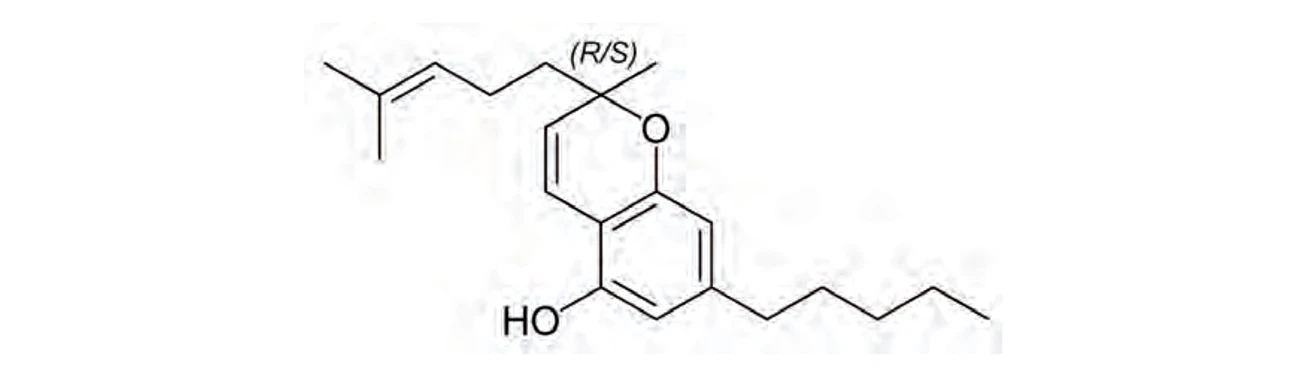

PČR: Kanabichromen (CBC) – má protizánětlivé a analgetické účinky (15)

PČR: Kanabichromen (CBC) – má protizánětlivé a analgetické účinky (15)